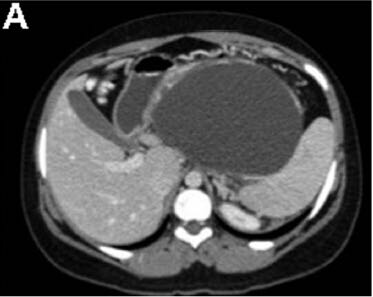

3个月前,她被电击中摔伤了腹部。当时这引起了上腹部疼痛;然而,她没有立即去医院直到3个月后才就诊。 该患者之前没有明显的病史或手术史,是一个非吸烟者,偶尔饮酒。 身体检查发现该女性健康,营养状况良好,唯一值得注意的是,腹部浅触诊时可于上腹部触及一个明显的肿块。 血常规检查包括全血细胞计数,尿素氮,电解质,葡萄糖,以及肝功能检查,均在正常范围内。血清淀粉酶66U/L,白蛋白43g/L,HIV 1/2 Ab/Ag酶联免疫吸附试验为阴性。 腹部对比增强计算机断层扫描显示连续轴向截面如图A-D。图E为矢状面。 剖腹手术时吸出低黏度,清澈,囊液,囊液生化分析显示,淀粉酶58903U/L,乳糖脱氢酶904U/L,蛋白质<10g/L。未获取囊性癌胚抗原和CA-19-9。在剖腹手术时对多个囊壁活检取样(图F)。

计算机断层扫描证实源自胰尾的一个大型,单房,囊性肿块,伴未分隔的附壁结节,或囊性钙化。影像学结果,临床病史,和囊液分析支持胰腺假性囊肿的诊断。出人意料的是,囊壁活检显示为良性粘液分泌柱状上皮,雌激素受体阳性,与良性粘液性囊壁肿瘤(MCN)一致。最终,执行远端胰腺切除术,并且此后恢复良好。鉴于MCNs已经确定的恶变可能(6%-27%的病例),这例患者“有惊无险”,按照计划因假囊肿接受胰囊肿胃吻合引流术可以避免恶性肿瘤转化的严重后果。